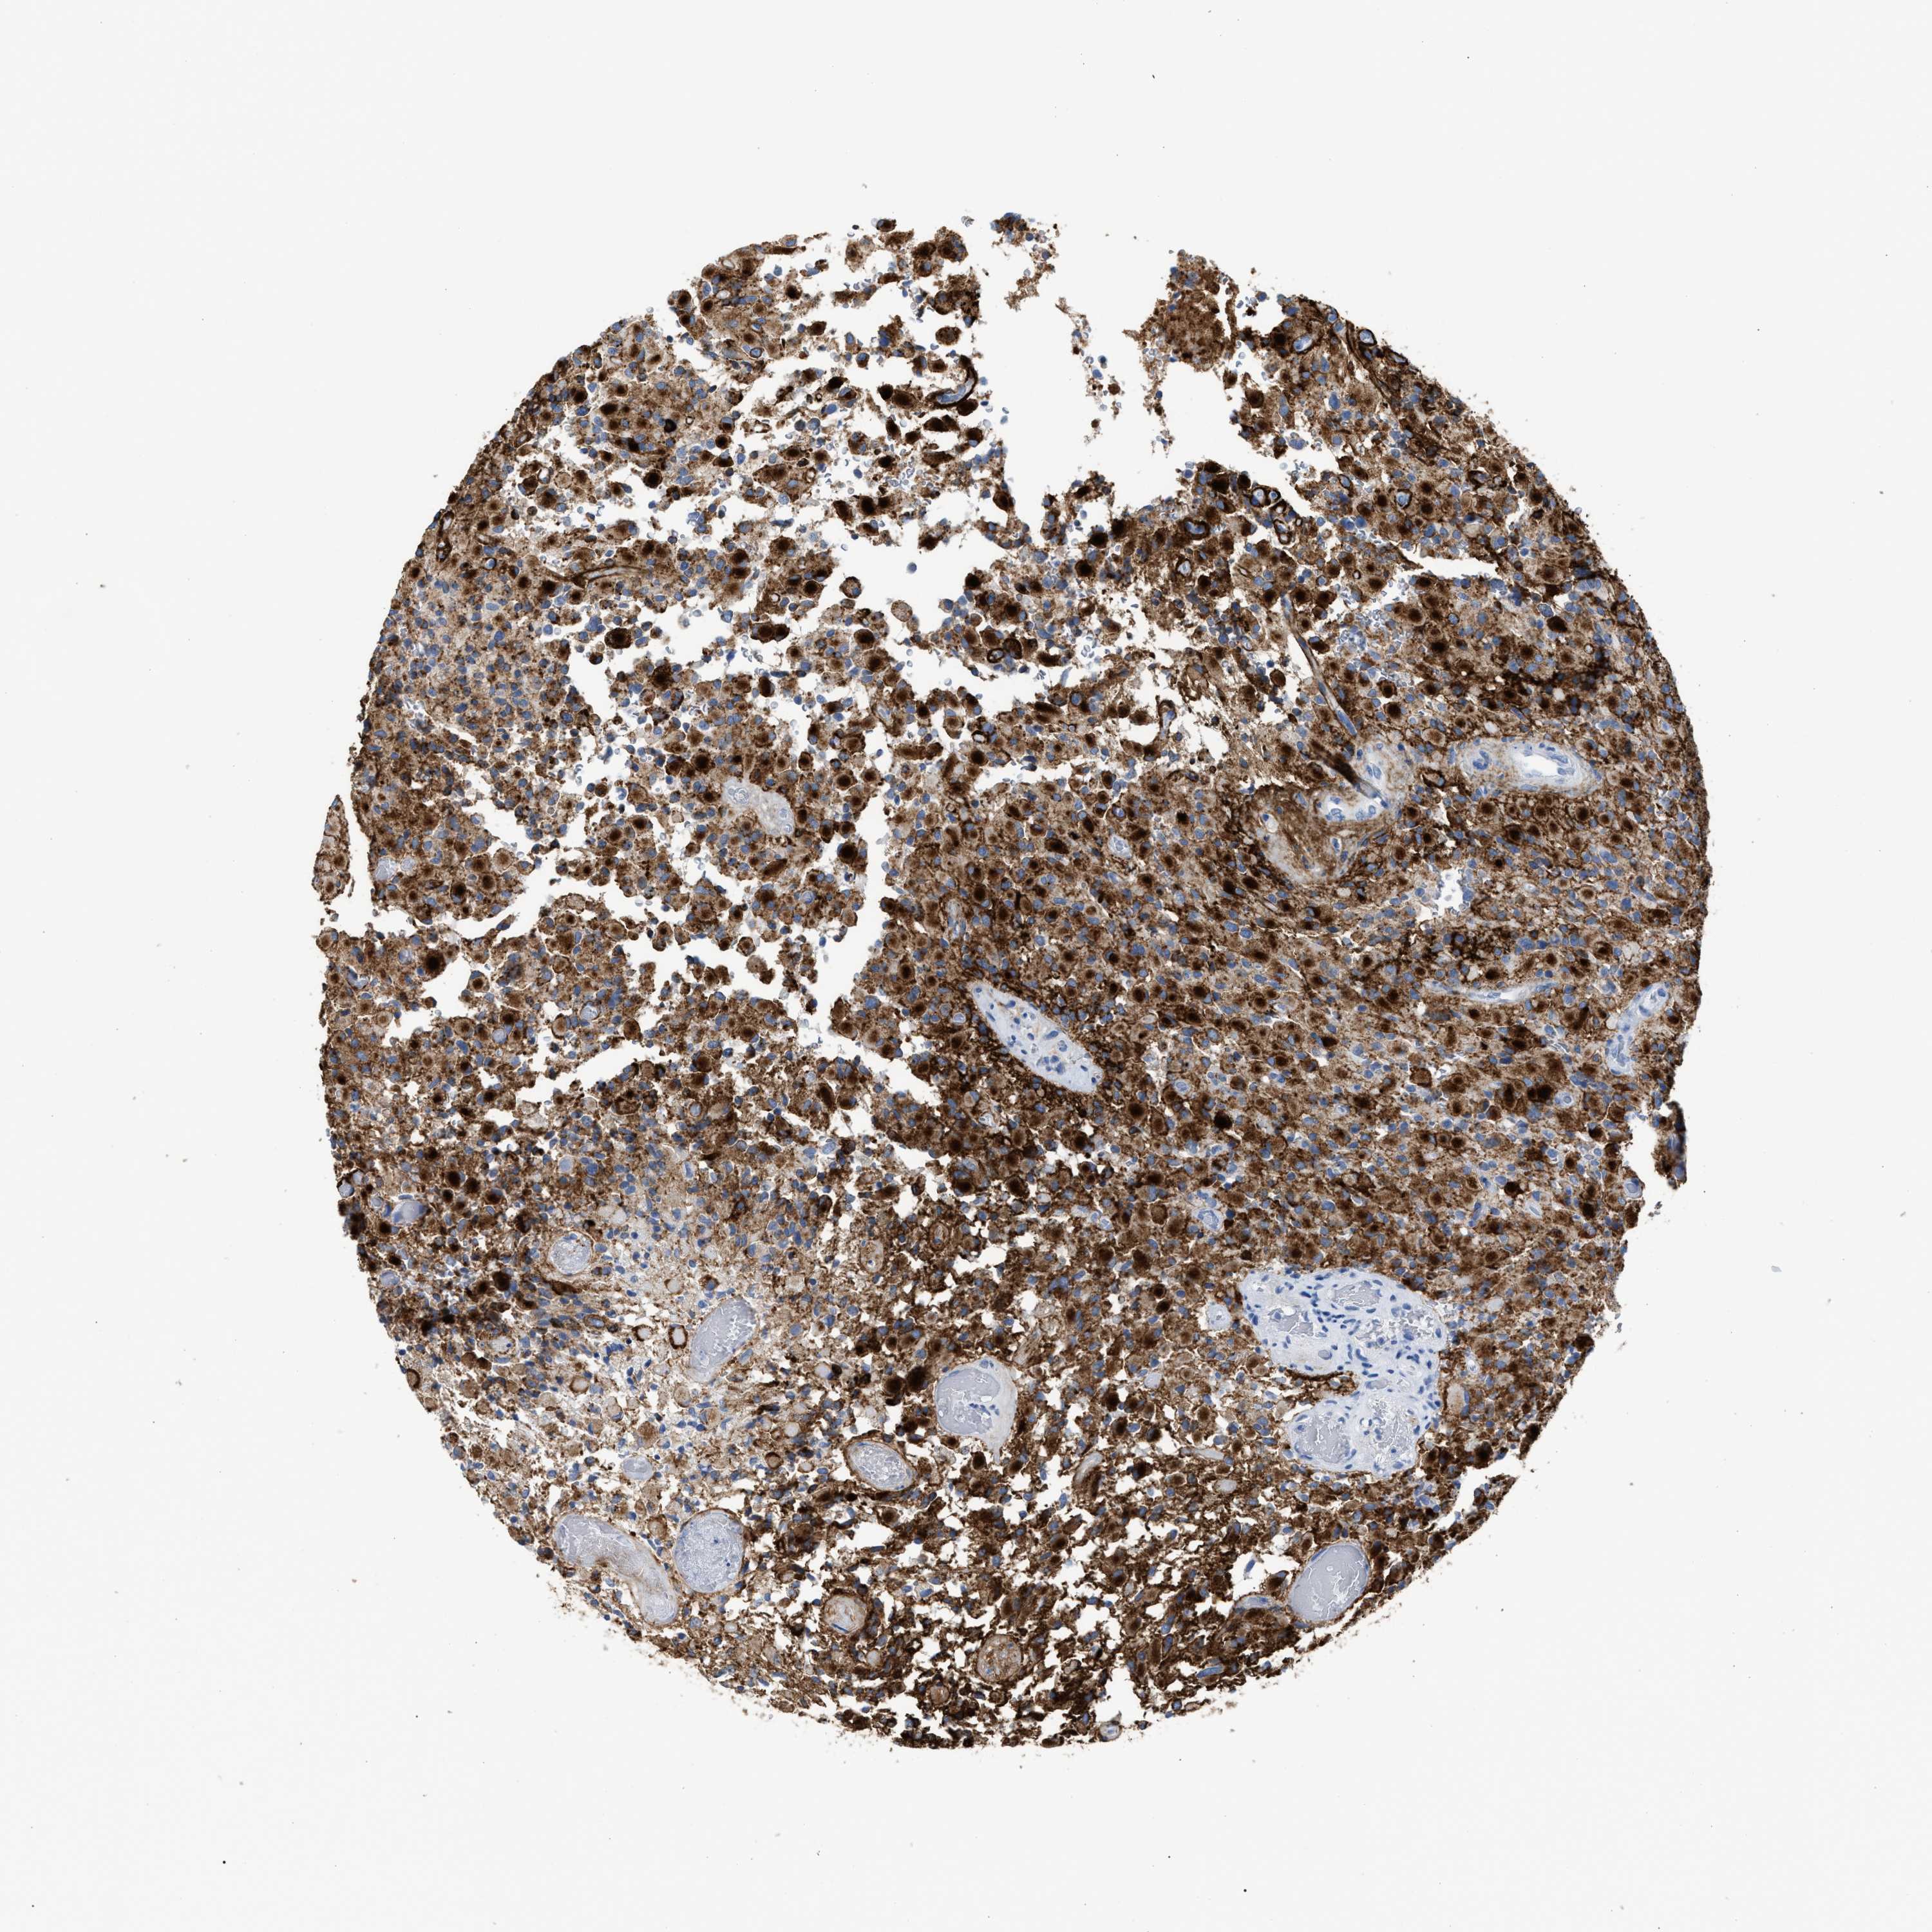

GLIOMA - Protein expressioni

A mouse-over function shows sample information and annotation data. Click on an image to view it in a full screen mode. Samples can be filtered based on level of antibody staining by selecting one or several of the following categories: high, medium, low and not detected. The assay and annotation is described here.

Note that samples used for immunohistochemistry by the Human Protein Atlas do not correspond to samples in the TCGA dataset.

Antibody stainingi

Antibody staining in the annotated cell types in the current human tissue is reported as not detected, low, medium, or high, based on conventional immunohistochemistry profiling in selected tissues. This score is based on the combination of the staining intensity and fraction of stained cells.

Each image is clickable and will lead to virtual microscopy that enables deeper exploration of all samples and also displays staining intensity scores, fraction scores and subcellular localization as well as patient and tissue information for each sample.

Antibody HPA027134

Antibody HPA027150

Antibody HPA029859

Antibody CAB022343

Staining

High

Medium

Low

Not detected

Intensity

Strong

Moderate

Weak

Negative

Quantity

>75%

75%-25%

<25%

None

Location

Nuclear

Cytoplasmic/membranous

Cytoplasmic/membranous,nuclear

Glioma, malignant, High grade

Glioma, malignant, Low grade

Glioblastoma, NOS